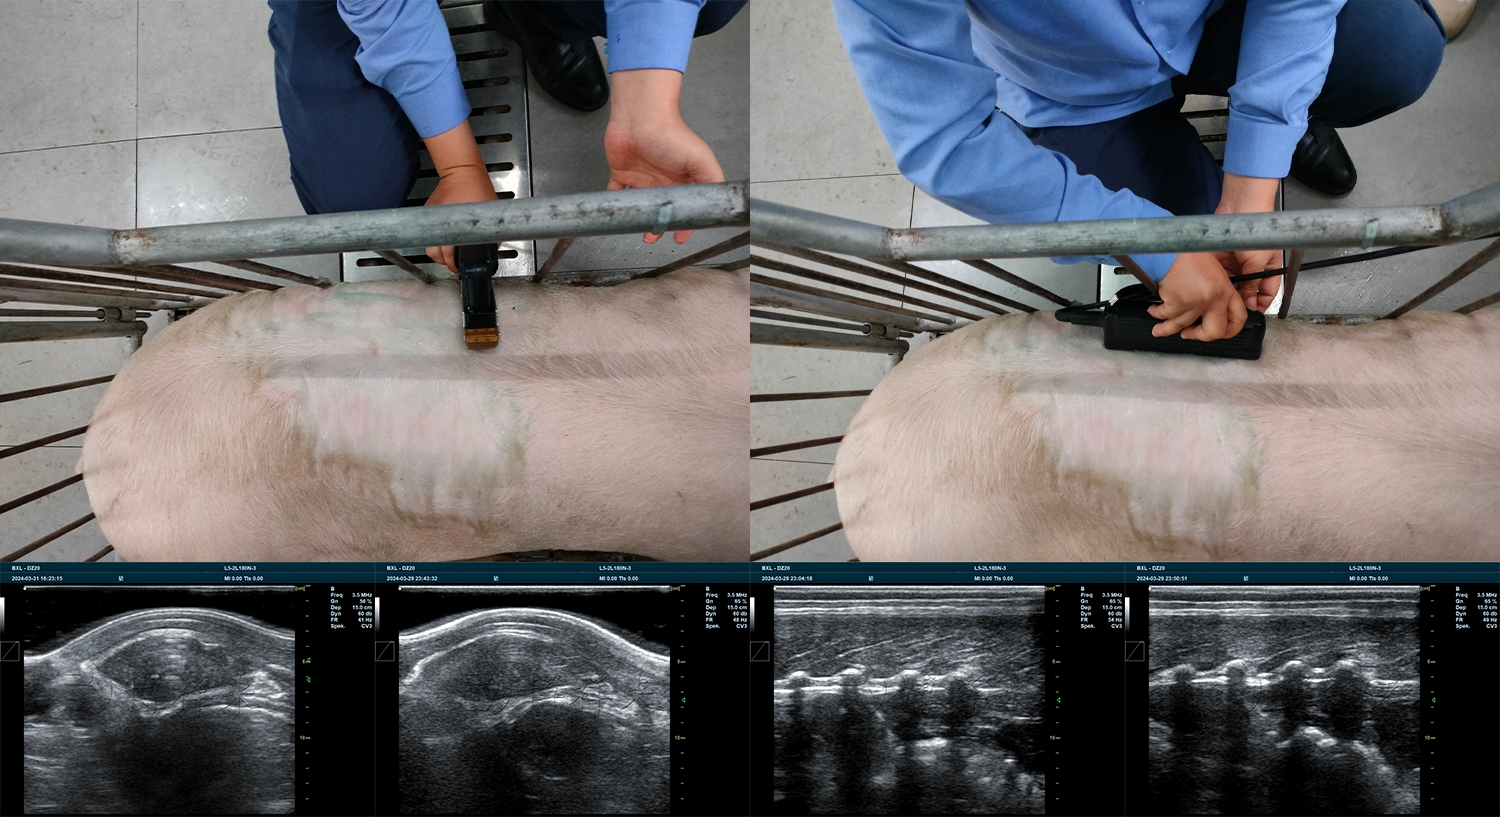

直肠探头(用于母猪妊娠检测)

背膘眼肌探头(用于体况评估)

看起来都是“探头”,但在实际使用中差异非常明显:

探头阵元数量

声束控制方式

长时间高频使用的稳定性

防水、防腐蚀能力

这些都会直接影响成像质量和使用寿命。